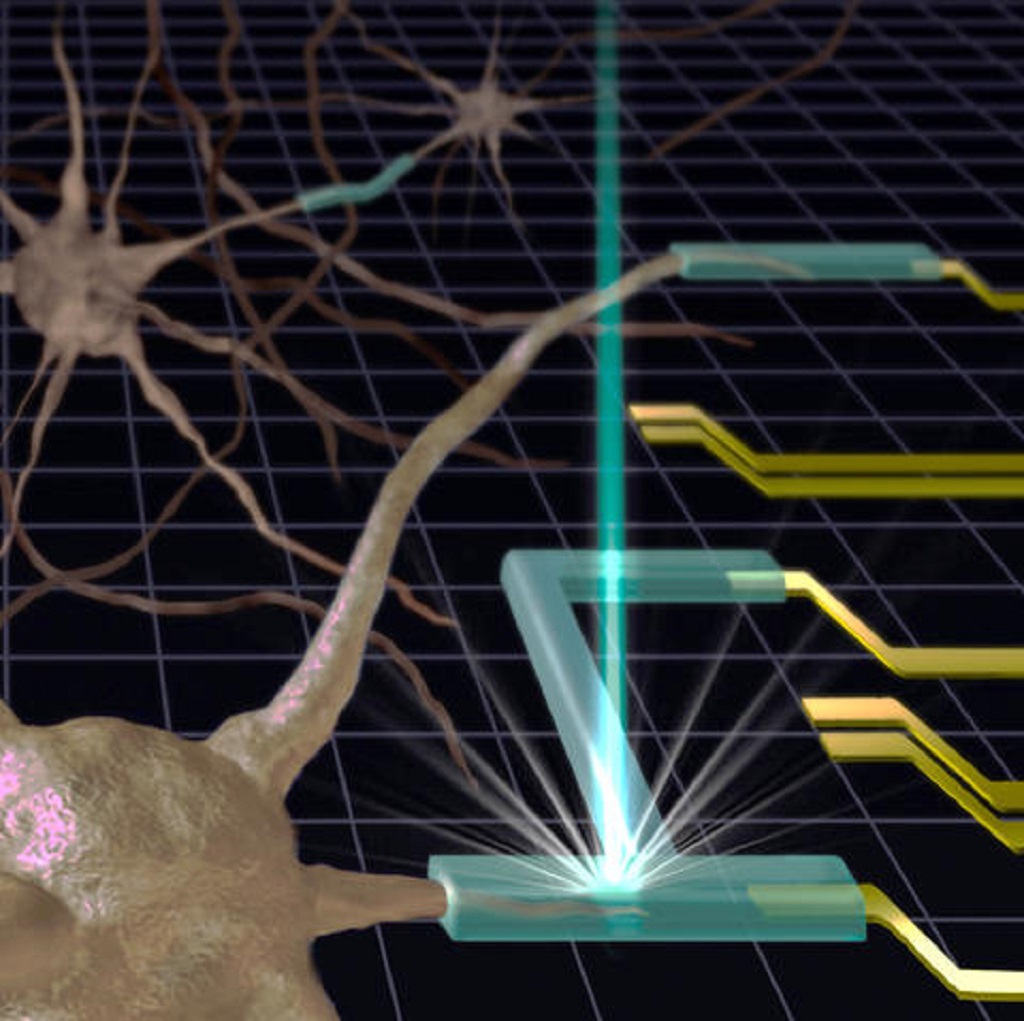

Two Photon Printing Microdevices Inside Living Cells

Two photon polymerization has now moved from “on cells” to “inside cells”, opening a strange, new frontier.

Researchers 3D Print Microstructures Inside Living Human Cells for the First Time

Researchers have 3D printed structures inside a living cell.

3D Printed Bioelectronics Are Coming

New research seems to have developed a way to 3D print bioelectronic components.